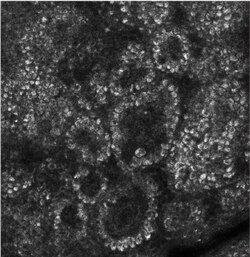

In dem auch als „Stachelzellschicht“ bezeichneten Stratum spinosum sind die Zellen durch Zytoplasmaausläufer mit Desmosomen verbunden. Hier beginnt bereits der als Keratinisierung bezeichnete, schrittweise Verhornungsprozess. Da die Zellen bei einer histologischen Verarbeitung schrumpfen, haben sie im Präparat ein stacheliges Aussehen. Im Stratum spinosum befinden sich zudem Abwehrzellen des lymphatischen Systems, die als Langerhans-Zellen bezeichnet werden.